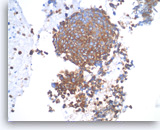

Pancreatic endocrine neoplasm #1,

Pancreas FNA, Cell Block.

The synaptophysin immunostain shows cytoplasmic positivity in the tumor cells, indicative of neuroendocrine differentiation.

40X